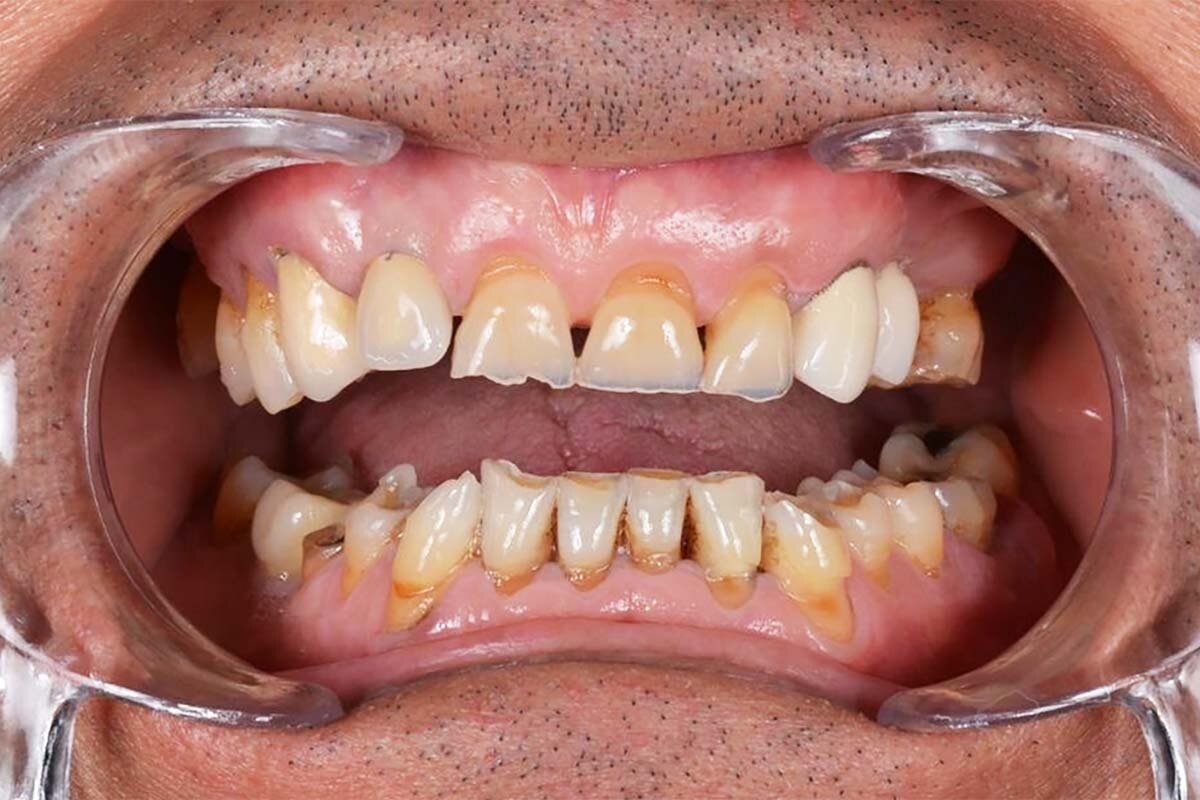

El bruxismo puede afectar progresivamente la salud dental. El roce constante entre los dientes desgasta el esmalte, debilitando su protección natural y aumentando el riesgo de fracturas, caries y sensibilidad.

Además, la presión continua puede dañar la articulación temporomandibular (ATM), generando dolor facial crónico y dificultades para masticar o hablar. En casos más graves, incluso puede modificar la forma del rostro debido a la tensión constante en los músculos de la mandíbula.